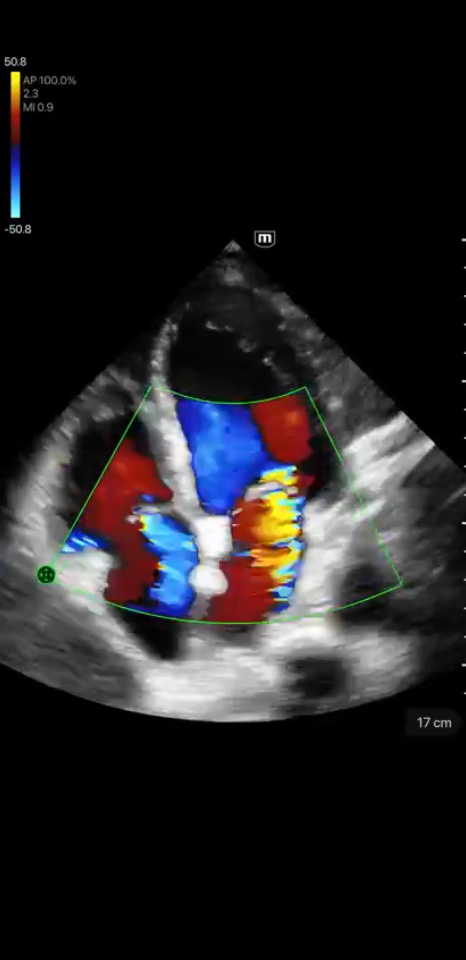

Immagini cliniche

Rigurgito mitrale e tricuspidale

Immagini cliniche

Rigurgito mitrale e tricuspidale